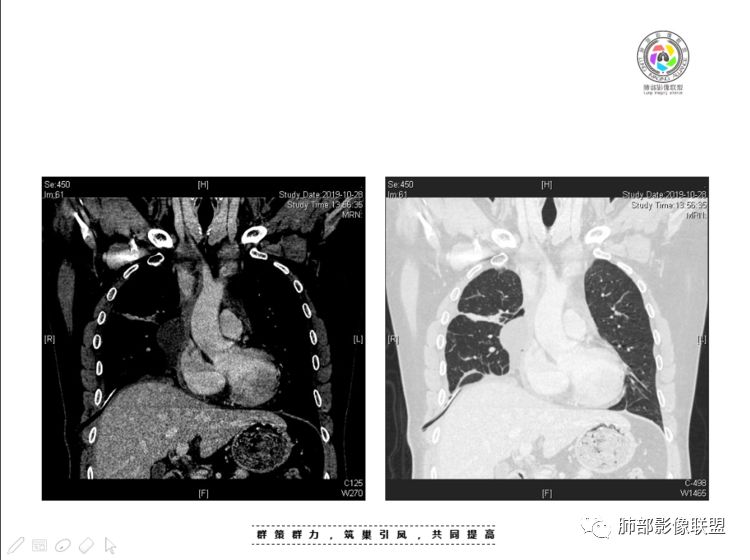

穿越七海的风:右前纵隔占位,恶性肿瘤,生殖来源?右肺实变是占位or肺不张?考虑为部分肺不张FeNo:右前纵隔占位,右肺结节,胸膜凹陷,小尾巴,右肺不张,考虑恶性杨旭华:恶性,前纵隔肿物,与血管关系密切,上腔静脉变窄,右肺野一元论考虑叶间裂增厚,恶性胸膜间皮瘤可能大小丽:到底是纵隔来源还是胸膜来源?我怎么倾向于胸膜来源,和叶间胸膜关系密切,而且纵隔内上腔静脉是向内侧推移。胸膜肿瘤(间皮瘤?SFT?)包裹性胸腔积液?马春平(张家港市一院胸外科):前纵隔占位,左无名受压,右大量胸腔积液可能是胸导管汇入处侵犯受压,考虑纵隔鳞癌孙冰伟:右上纵隔占位,也感觉和叶间胸膜关系密切,右侧胸膜局限性增厚,考虑恶性可能性大灵:前纵隔占位,血性胸水,胸膜凹凸不平,查见肿瘤细胞,结合免疫组化考虑胸腺癌。鉴别胸膜间皮瘤。采莲:右前上纵膈旁可见类圆形肿块,纵隔血管内移,感觉来源于胸膜,肿块内密度低,似水样密度,右侧胸膜广泛增厚,少量胸腔积液。心包少量积液。考虑胸膜间皮瘤,鉴别肺癌并胸膜转移?水晶石头:患者中年男性,胸闷15天。有“高血压、慢性肾小球肾炎”病史。查肿瘤标志物正常,胸水提示渗出液,胸水病理查见瘤细胞。胸部CT:右肺上叶后段结节、斑片影,见胸膜牵拉、包裹积液及部分纤维条索灶,似见卫星灶,右侧胸膜增厚。前纵隔脂肪密度增厚,右侧可见类圆形低密度(液体)肿块,边缘光滑。综合考虑右肺腺癌并胸膜转移,结核可能。周太狼:考虑纵隔胸膜来源肿瘤,恶性,胸膜间皮瘤伴转移?徐飞:中年男性,影像为右侧胸腔及叶间积液,叶间胸膜增厚轻度强化。前纵隔右侧心缘旁团块,可见坏死。胸水见癌细胞,综合考虑恶性,胸腺癌伴转移。小赵:中年男性,血性胸水,常规查见癌细胞,李凡他实验阳性。胸部CT示前纵隔见不均匀密度影,与邻近大血管分界不清,囊变坏死明显,增强扫描呈不均匀强化,心包及右侧胸膜增厚,并心包及右侧胸腔少量积液。综合考虑胸腺癌。右肺中叶病变周围见多发纤维条索,支气管部分进入病灶,考虑炎性病变。流心明智:患者,男性,50岁。胸闷15天。高血压20年,慢性肾小球肾炎15年。肿标正常,胸水提示渗出液,胸水查见癌细胞。胸部CT:右肺肿块影,斑片影,索条影,可见胸膜牵拉、多发包裹积液,纵隔上腔静脉受累,心包受累。综合考虑:ROSE似腺?考虑右肺腺癌并胸膜转移,心包受累。鉴别胸腺Ca、淋巴瘤,纵隔病变不懂,等老师们精彩分析。王秀仙:前纵膈囊实性肿块,与纵膈分界不清,心脏大血管及上腔静脉受压向内后移,右侧后胸膜、侧胸膜增厚,右侧叶间裂不规则增厚,心包积液,根据腔静脉移位情况,考虑纵膈胸膜来源恶性肿瘤,胸膜间皮瘤?鉴别胸腺癌并胸膜转移。高广飞:上纵隔占位,右侧叶间胸腔积液,需考虑恶性自信人生:多发囊实性病灶,包裹性积液,考虑胸膜来源 只是没有看到壁结节,恶性胸膜间皮瘤巴伟:前上纵隔占位,胸膜及心包结节,考虑胸腺瘤或癌,右肺病灶,先考虑陈旧炎性病变。Lenle董:前纵隔占位,部分边缘模糊,病灶内囊变?坏死?上腔静脉受侵,考虑胸腺癌;叶间片状影,强化明显,炎性考虑。常志强:前纵隔囊实混杂密度肿块,边界不清,实性部分强化明显,结合胸水内见癌细胞,考虑恶性肿瘤伴转移。飞鹰行动:前纵隔占位,软组织密度及囊性密度,实性部分密度均匀,致密,病灶与周围血管分界不清,增强后病灶强化有类似不温不火强化,部分血管受侵犯,右肺见肿块样病变及条索状病变,一元论,考虑淋巴瘤,二元论,考虑胸腺瘤B2—B3伴右肺病变。尽量一元论考虑,淋巴瘤可能。看图说话:右肺索条病灶,边缘膨隆,胸膜牵拉,考虑右肺癌伴胸膜转移。晨:前纵隔囊实性肿块,与纵隔分界不清,右侧后胸膜、侧胸膜增厚,右侧叶间裂不规则增厚,考虑纵隔胸膜来源恶性肿瘤,考虑胸腺癌并胸膜转移。丽:中年男性,前纵隔囊实性肿块,呈偏心性生长,临近大血管受压推移,增强后实性部分不均匀强化,心包可见条形积液,考虑胸膜来源恶性肿瘤,胸腺癌可能大。另右肺多发斑片状高密度影及实变密度影,实变影呈均匀强化,右侧胸膜局限性增厚,考虑炎性病变。小飞:右前纵隔囊实性占位,实性部分明显强化,右侧叶间胸膜增厚,右侧胸腔积液,心包积液,考虑恶性胸腺瘤!尘缘:支持恶性胸腺瘤(囊实性肿块,实性强化,且侵犯纵隔,脂肪间隙模糊)伴肺内及胸膜转移。浪迹天涯:考虑侵袭性胸腺瘤——胸腺前纵隔占位,周围脂肪间隙模糊不清。尘缘:不除外另一种可能:二元,肺内腺癌合并胸膜转移,纵隔的畸胎瘤可能。一米阳光:晨读中年男性,右肺结节影,叶间裂及胸膜增厚牵拉,右侧胸水。心包多发结节改变。胸水查见癌细胞。考虑,腺癌并转移。鉴别,胸膜间皮瘤并转移前纵隔囊实性占位,二元考虑。心灵鸡汤:老年男性,右肺中叶外段长条状软组织密度影,边缘膨隆,邻近胸膜牵拉,部分胸膜有栽脏,右中叶外侧段支气管堵塞,常规考虑恶性肿瘤,腺癌可能,结核、鳞癌不除外,另右肺上叶斑片影,小叶性肺不张?右前纵隔囊实性不规则形密度影,其内见部分脂肪样极低密度影,与邻近血管边界不清,心包外膜有侵犯,增强未见纵隔窗平扫,实性及分隔见增化,其内低密度影未强化,考虑低度恶性纵隔肿瘤,间皮瘤可能,畸胎瘤、淋巴瘤待排,建议支气管镜及穿刺活检。曹志勇:右前纵隔考虑来源于胸膜的恶性肿瘤,右肺内病灶考虑鳞癌,二元德芙~云味:中年男性,右肺见结节、斑片影,右侧包裹积液、胸膜牵拉,纤维条索,前纵隔囊性占位,考虑腺癌、并转移。欧阳英:右前中纵隔囊实性肿块及右肺内结节灶,支持恶性肿瘤,胸腺癌并肺内转移可能张延军:前纵隔见不规则软组织影,密度不均,右侧缘见囊变区,纵膈及侧胸壁胸膜增厚,增强呈不均匀强化,右肺中叶见结节灶,近段支气管阻塞,叶间胸膜不规则增厚,考虑1:右肺中叶腺癌伴纵膈及胸膜转移;2:前纵膈侵袭性胸腺瘤并胸膜侵犯,中叶炎性改变?彭君:老年,前纵隔占位 ,坏死边缘清, 侵犯心包 右侧胸膜及叶间胸膜结节 ,少量胸水, cea不高 ,考虑恶性, 间皮瘤可能 ,转移待除外。毛勤香:恶性没问题,胸水查见癌细胞,一元还是2元,右肺中叶肿块,边缘毛糙,局部似有毛刺,周围有粘连,右侧胸膜腔少量积液,胸膜增厚多发结节,含叶间裂结节,纵膈脂肪间隙模糊,纵膈胸膜增厚,心包增厚积液,右前那个类圆形低密度肿块,纵膈血管内移,我考虑胸膜来源可能性大,综合考虑,一元肺腺癌并多发转移,二元考虑胸膜间皮瘤并多发转移,肺内炎症不张。

南边:大家看看前纵隔的病灶,符合肿瘤吗脂肪,周围密度增高

三个石头:比较散;像炎症的蔓延生长南边:是,这些看着心里不踏实觉得把这个纳入肿瘤去考虑是否合适总觉得边缘收缩的、散在的朝周围蔓延;中央还跨过脂肪,朝对侧胸膜蔓延把这个与囊性病变连到一起去考虑是否还需要斟酌一下因为这个就方向差异大了南边:连在一起,囊实性,边界不清,自然考虑恶性:如果独立,囊张力高、边界清楚,间隔,自然朝良性考虑:

我认为囊张力高,积液中的气体均在周围,外侧、下方,囊内有间隔:各腔密度不一致;提示:囊腔属于前纵隔,不是包裹性积液;现在的问题:囊腔与内侧的病灶是否是一体的

南边:我总觉得这个纵隔内不像是一个肿块的改变,扁平,周围蔓延:有符合炎性的的特点,或者肿瘤的侵犯;但是肿瘤的侵犯,不大符合,实性部位的边缘过于柔和,没有毛糙的侵犯边缘。

本例纵隔与肺内两处病变,回顾总结分析:

2、前纵隔内病灶囊实性混杂密度病灶,囊性病灶主要位于右侧,张力较高,有分隔影,囊壁右侧缘光整,病灶左侧实性部分边界不清明显强化,病灶肺瘤交界面大部分边界清楚,部分模糊。

纵隔内病灶不符合肺癌转移途径,且纵隔内单发的囊实性转移罕见。淋巴瘤无论是分布、形态、密度、还是强化方式度不符合。

胸腺瘤/胸腺癌:病灶内那么大的囊,常规考虑B型以上胸腺瘤,囊内有分隔影,病灶周围脂肪间隙模糊,常规考虑侵袭性胸腺瘤或胸腺癌,若侵袭性胸腺瘤,常侵犯胸膜、心包,很少累及肺。胸腺癌易侵犯胸膜、肺并纵隔淋巴结及远处转移。但肺内腺癌形态更符合原发灶。胸膜及叶间裂转移则即可来自肺,也可来自胸腺癌。

尽管前纵隔病灶缺乏相关病理资料,但是小编还是认为肺内与纵隔病灶以二元论解释。只是肺内恶性病灶引发的胸膜改变可能会影响我们对纵隔病灶的判断。